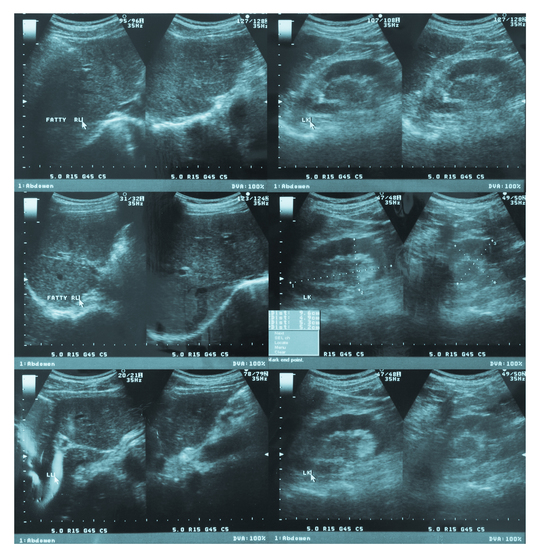

Биопсия была назначена на понедельник, в выходные я принимала ношпу и ставила свечи с папаверином во избежание возможного тонуса. В понедельник утром я приехала в больницу, имея при себе помимо документов, копии анализов крови на ВИЧ, гепатит, группу крови и мазка на степень чистоты, воду, халат, тапочки, еду не стала с собой брать, хоть это и было в рекомендациях. Нас собралась целая группа, человек 12, все на разных сроках, с разными рисками и возможными диагнозами. Сначала мы все, в порядке очередности сходили на УЗИ (перед этим измерили температуру и давление). После УЗИ отсеялось человек пять, по причинам тонуса, несоответствия срока для конкретной процедуры или признаков заболевания мамочки (температура, давление, кашель). Оставшихся проводили в палату, где мы переоделись в халаты и тапочки и пошли к операционной, куда заходили в порядке живой очереди. Во время самой процедуры я очень пожалела, что увидела толщину иглы, мне она показалась целой спицей! От страха я напряглась, поэтому сам прокол получился довольно болезненным. К игле прицепили какой-то механизм, с помощью которого врач начал отщипывать кусочки плаценты. Все проходило под контролем датчика УЗИ, первая же полученная порция материала тут же была отправлена под микроскоп, для определения количества и качества ворсинок. Мне повезло как утопленнику, отщипнуть смогли только короткие ворсинки, поэтому процедуру биопсии (не вытаскивая иглу) пришлось повторить трижды. Было не столько больно, сколько страшно и противно, было ощущение, что из меня через живот пытаются вырвать матку. В итоге я начала терять сознание из-за понижения давления, врачи сжалились и прекратили мою экзекуцию, отпоили нашатырем и отправили в палату. В палате было положено отдыхать час-полтора, после чего идти на контрольное узи. Через полтора часа дискомфорт в животе прошёл, давление и общее состочние пришло в норму и я пошла на УЗИ, где тот же врач показал, что все хорошо, ребёнок не отреагировал, включил мне сердцебиение. В конце отдали результаты обоих УЗИ и отправили домой, ждать результатов. В пятницу я уже дозвонилась до больницы, узнала, что результат готов и снова поехала на приём к генетику.

В назначенный день я приехала в клинику, подготовка к процедуре ничем не отличалась от моего первого раза, за исключением того, что врачи меня уже узнали, а я с ними уже вполне по-дружески общалась) кордоцентез мне понравился больше, чем плацентецентез. Был сделан прокол в самом низу живота, и врач под контролем УЗИ в течении 4-5 минут пытался попасть в пуповину, временами больно, но в основном неприятно. Но организм, уже видимо по привычке, попытался потерять сознание, был откачен нашатырем и отправлен в знакомую палату. Через полтора часа — контрольное УЗИ, ребёнок снова не отреагировал на процедуру, вел себя спокойно, сердечко даже не ускорило свой ход.